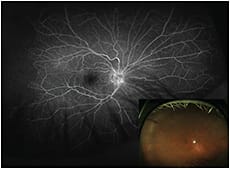

Figure 1. Wide-field image, using fundus flourescein angiography (FFA right eye).